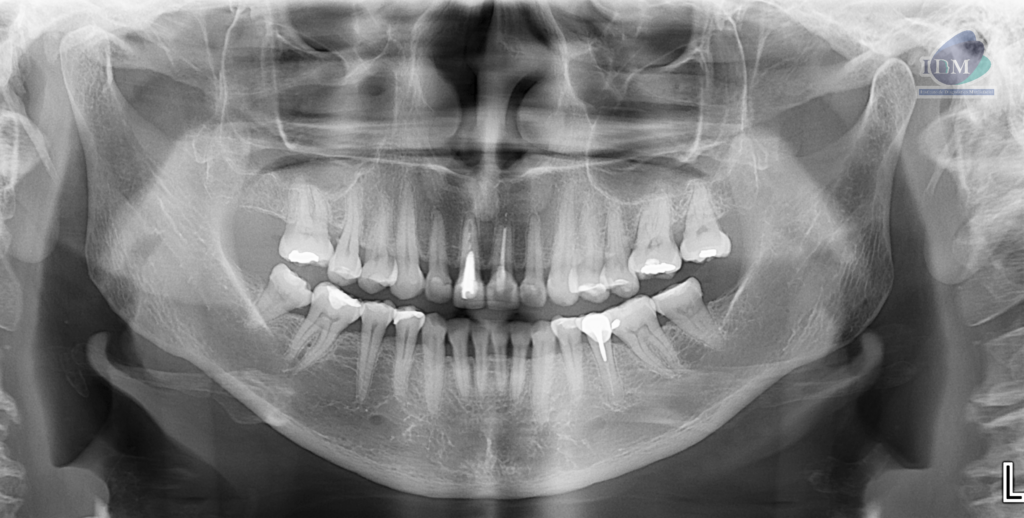

En la radiografía panorámica (Figura 1), se observa pieza 11 con corona protésica, espigo intrarradicular y obturación parcial de conducto y pieza 21 con corona protésica, obturación de conducto y disminución de la densidad en tercio apical.

Radiografia Panorámica